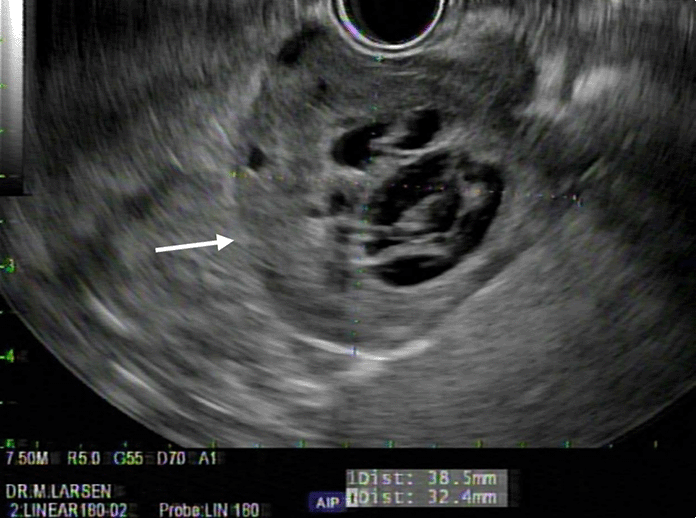

Endoscopic ultrasound demonstrating 3.8 × 3.2 cm hypoechoic, multicystic, lobulated mass arising from lesser curvature of stomach

To better characterize the mass, the patient was referred for upper GI endoscopy. The study demonstrated a subepithelial lesion on the lesser curvature of the stomach with an area of central umbilication. The patient also underwent endoscopic ultrasound (EUS), which showed a 3.5 × 3.2 cm, hypoechoic, multicystic, septated mass (Figure 2). The lesion appeared to originate from the muscularis propria with well-defined borders. Multiple biopsies were taken, and tissue was sent for pathologic interpretation. Immunohistochemistry (IHC) was performed, which stained positive for CD31 and negative for c-KIT, PDGFR, and DOG-1. CD31 positivity suggested this to be a highly vascular lesion as CD31 is an endothelial cell marker. The lack of expression of c-Kit, PDGFR, and DOG-1 made our presumptive diagnosis of a GIST less likely. Importantly, staining for S-100 was not performed at this juncture. Thus, the working pathological diagnosis was gastric hemangioma. The mass, however, did not appear to have the physical characteristics of hemangioma during endoscopic visualization. Given the size and the endoscopic characterization of the mass, the decision was made to offer the patient surgical resection of the lesion without a definitive diagnosis.